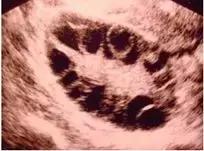

B超可以发现以下疾病:

卵巢多囊样改变